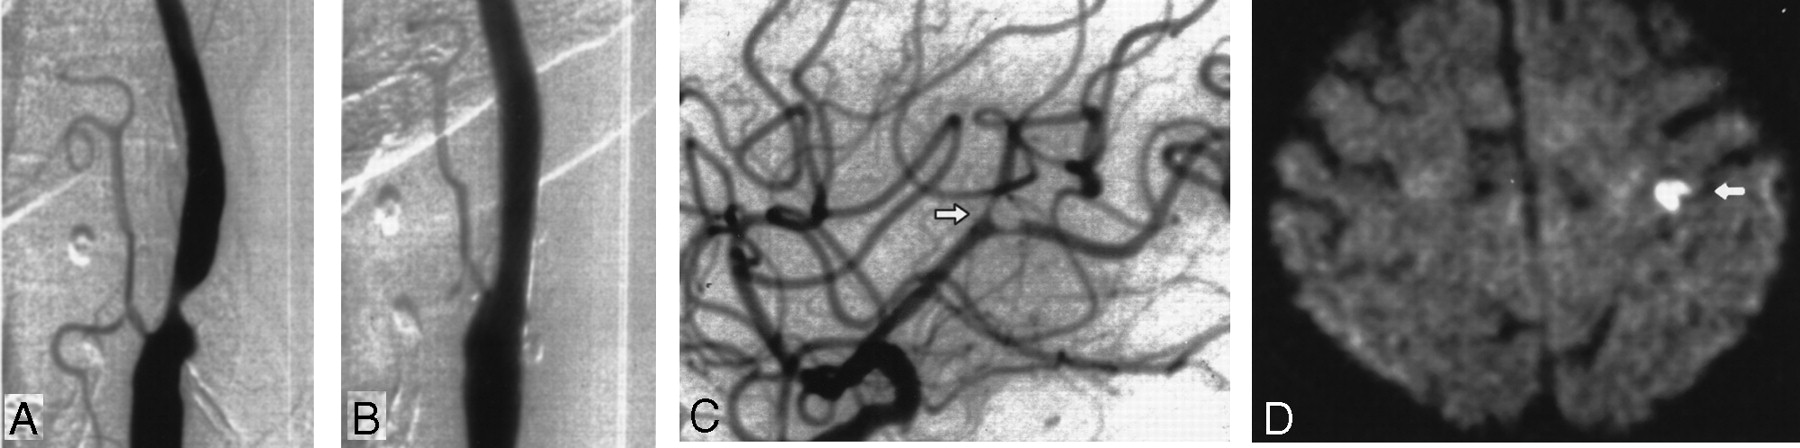

Images obtained in a 76-year-old woman with a symptomatic stenosis of the carotid artery.

A, Left anterior oblique angiogram shows a 79% stenosis of the left ICA.

B, Left anterior oblique angiogram shows the result after stent implantation.

C, Lateral angiogram shows the intracranial circulation of the treated side after a procedure with a nonocclusive embolus in a branch of the MCA (arrow). The patient was symptomatic during the whole procedure. An angiogram of the intracranial circulation obtained after the infusion of 100,000 IU of urokinase into the ICA demonstrated complete disappearance of the embolus (not shown).

D, Postprocedural axial diffusion-weighted MR image (6000/103/1) shows eight new ipsilateral lesions (5–10 mm) in the cortical territory of the MCA (arrow).